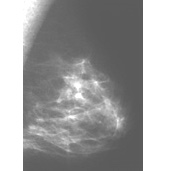

On the mammogram, there are two principal signs of cancer: calcifications and/or the presence of a mass. Calcifications (deposits iof calcium compounds in the breast) show up as white spots on a mammogram and occur in two forms, microcalcifications and macrocalcifications. Macrocalcifications tend to be large and coarse looking and are associated with aging. They are common in women over 50, and are present in a small percentage of younger women. Macrocalcifications are not typically associated with cancer. Microcalcifications are smaller and are considered a sign of possible malignancy, even without a visible mass. The radiologist must interpret the characteristics of the mass to determine the possibility of cancer, and will order diagnostic tests and possibly a biopsy.2

The image on the left shows the mammogram of a normal breast, while the image on the right shows a mammogram with an abnormality detected (denoted by the red arrows). Click on the images to visit their source, the Breast Center of St. Louis University.